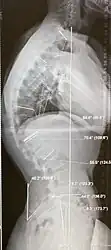

Diagnosis is typically by medical imaging. The degree of kyphosis can be measured by Cobb's angle and sagittal balance.

-

Scheuermann's disease, showing various measurement of kyphotic/lordotic degrees and their supplementary angles. Notice the signature 'wedging' shape of the four vertebrae in the lower thoracic area. The other vertebral bodies are otherwise normal. -